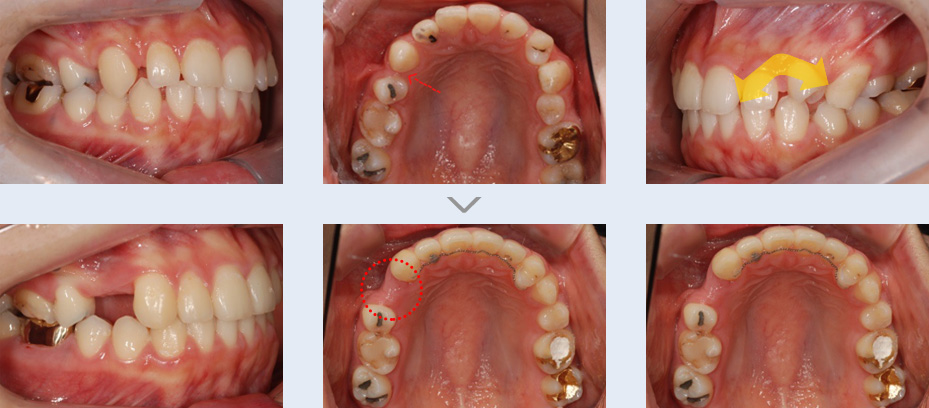

왼쪽 위 치아들의 모양과 위치가 정상적이지 않았고 치열이 대칭적이지 않아 교정 치료를 권유 받고 내원한

학생입니다. 좌측 위 송곳니와 작은 어금니의 위치가 바뀌어 있고 우측 작은 어금니가 결손되어 주위 치아들이

기울어져 있으며 틈새가 벌어져 있습니다. 고정식 교정 장치를 이용하여 치열을 고르게 하고 결손된 치아 공간을

재배치하였습니다.

비대칭 모양의 치열을 대칭 형태로 개선하였고 송곳니와 작은 어금니의 위치를 정상적으로 되돌렸습니다. 또한

결손된 치아 위치는 성인이 된 후 임플란트를 식립할 수 있도록 유지 관리하였습니다.